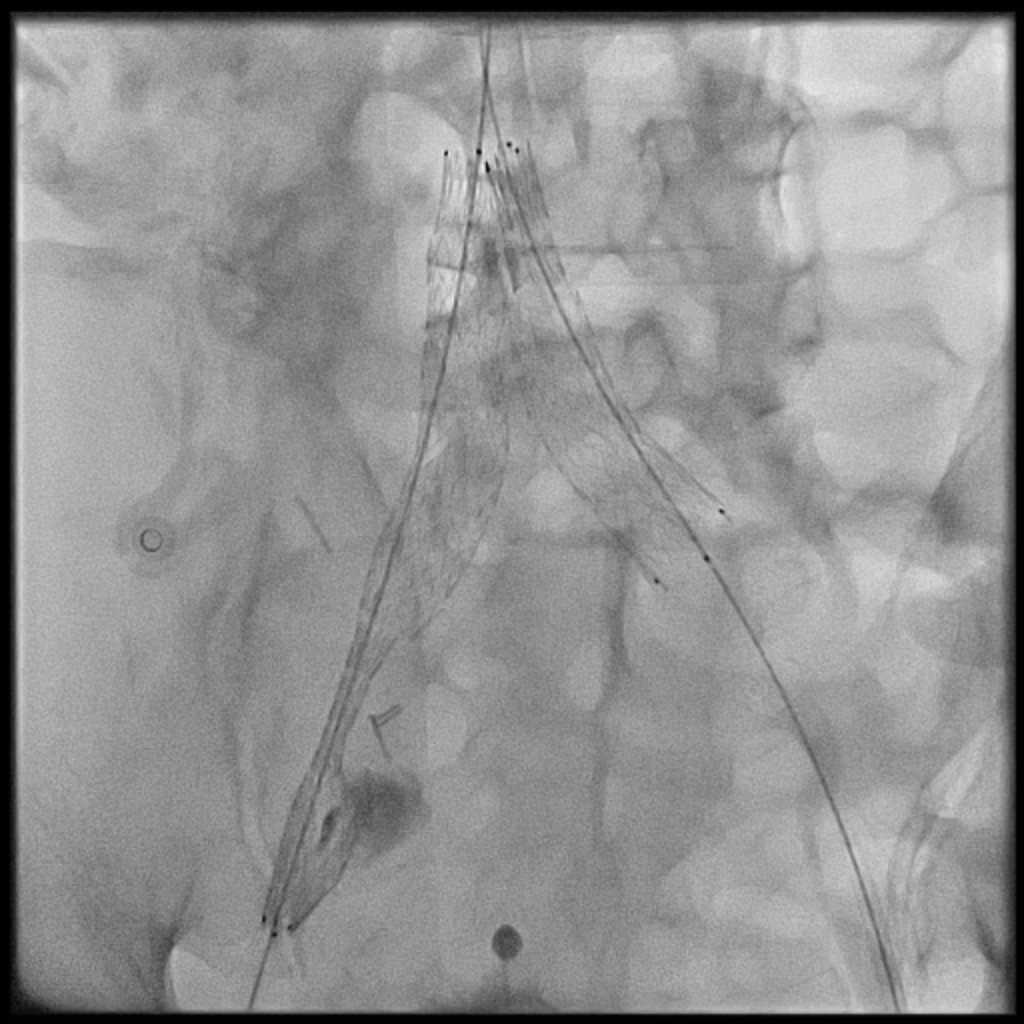

Venous access was obtained and venography confirmed heavy thrombus burden; therefore, the initial 6 Fr sheath was upsized to a 9 Fr sheath. Two Terumo stiff wires were advanced into the IVC to secure stable access. Mechanical thrombectomy using the Boston Scientific AngioJet system was performed from the right iliac vein to the right common femoral vein. During venography, unexpected early arterial opacification suggested an iatrogenic artery-to-vein fistula. Iliac angiography was then performed, revealing a total occlusion of the right common iliac artery with collateral reconstitution. To restore arterial flow and seal the fistula, a contralateral approach was used. A wire successfully crossed the occluded segment into the true lumen, followed by deployment of a covered stent. Final angiography showed complete closure of the fistula and restored antegrade arterial flow without distal embolization. The patient remained hemodynamically stable.